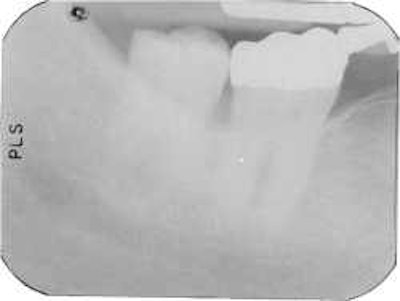

![]() |

| A typical underexposed shot. These images cannot be corrected digitally. |

Exposure errors. Once again, says Williamson, don't rely on default settings. "Look at your subject! A big guy needs a longer exposure, a small 80 year old woman, much less," says Williamson. Underexposed shots can't be corrected digitally, she says. Overexposed pictures can be fixed. "But the more you fuss with an image, the worse it gets."